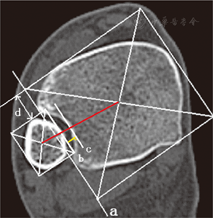

(1)下胫腓联合形态的分型:选取每例患者水平位CT平扫数据,选取距离胫距关节面9~11 mm的CT扫描图像进行影像学分析。根据腓骨在胫骨下端所形成的曲度,将其分为半圆形、新月形和矩形三种形态。(2)胫腓骨中心距离测量[9]:选取距离胫距关节面9~11 mm的CT平扫图像进行参数测量。首先,在下胫腓联合平面作切线a,然后平行于该线分别作腓骨和胫骨内外侧边缘的切线,垂直于切线a作胫骨及腓骨前后缘切线,从而形成两个包绕胫骨和腓骨的四边形;最后,连接两个四边形的对角线,其交叉点分别为腓骨及胫骨的中心,测量胫骨中心至腓骨中心的距离。(3)胫腓骨间隙宽度测量[9]:平行于切线a分别作腓骨内侧缘及下胫腓联合内侧缘的切线b和c,测量两线之间的垂直距离。(4)胫腓骨前缘距离测量[9]:测量胫骨前缘切线及腓骨前缘切线之间的垂直距离d。见图1。